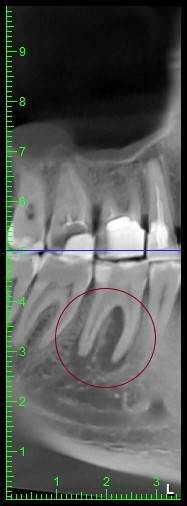

КТ от 04.03.2024

69273_3.jpg.f56a31dc1d8d53085767a9a52915128c.jpg69273_4.jpg.f9ec255bedbdb9fde8159318d3cb1fd9.jpg69273_5.jpg.36a7a942d403dd2eb062e5a4b2b58a52.jpg69273_6.jpg.492d3fbca3808fbdf58c86056b2fe0c3.jpg69273_7.jpg.f9bfdd5d593504dc7bd3710ece18aa4f.jpg69273_8.jpg.853e2342e6f2329a2e89c8939c2aad6f.jpg69273_11.jpg.e495813d50bf007f7165bf5f5dfec4b3.jpg69273_12.jpg.49b3cf66b4dd26b5cd68a91b2684e402.jpg69273_13.jpg.5d61b621b8e8b2c473ad6a8aca42502d.jpg